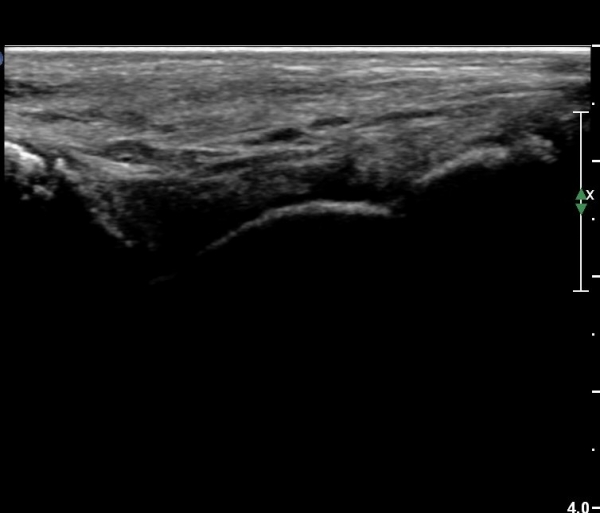

Àü¹æ °æ°ñºñ°ñÀδë Á¾´Ü¸é°Ë»ç¿¡¼­ ƯÀÌ ¼Ò°ßÀ» º¸ÀÌÁö ¾Ê´Â´Ù(»çÁø 3).

Àü°ÅºñÀδë Á¾´Ü¸é°Ë»ç¿¡¼­ ¾È´ë ºñ°ñ ºÎÂøºÎÀÇ Àú¿¡ÄÚ ºÎÁ¾°ú ºÎºÐÆÄ¿­ÀÌ °üÂûµÈ´Ù(»çÁø 4).